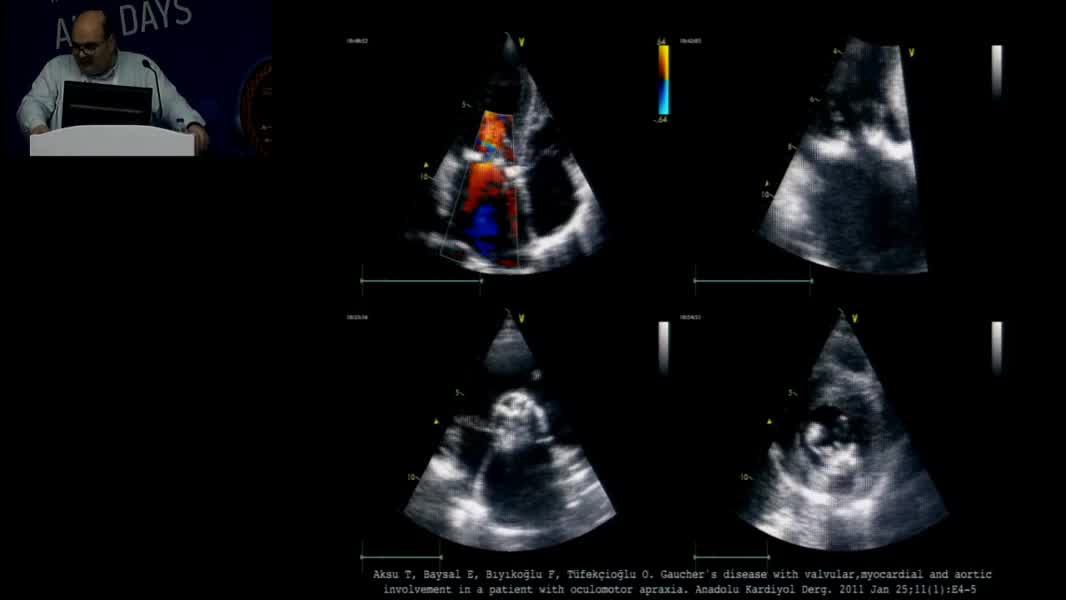

Echocardiographic Face Of Rare Cardiomyopathy And Fabry: Hands On Practical Echocardiography Course In The Diagnosis Of Fabry Disease And Cardiomyopathy Omaç Tüfekçioğlu (TR)

Nadir Miyokardiyopati ve Fabry’nin Ekokardiyografik Yüzü